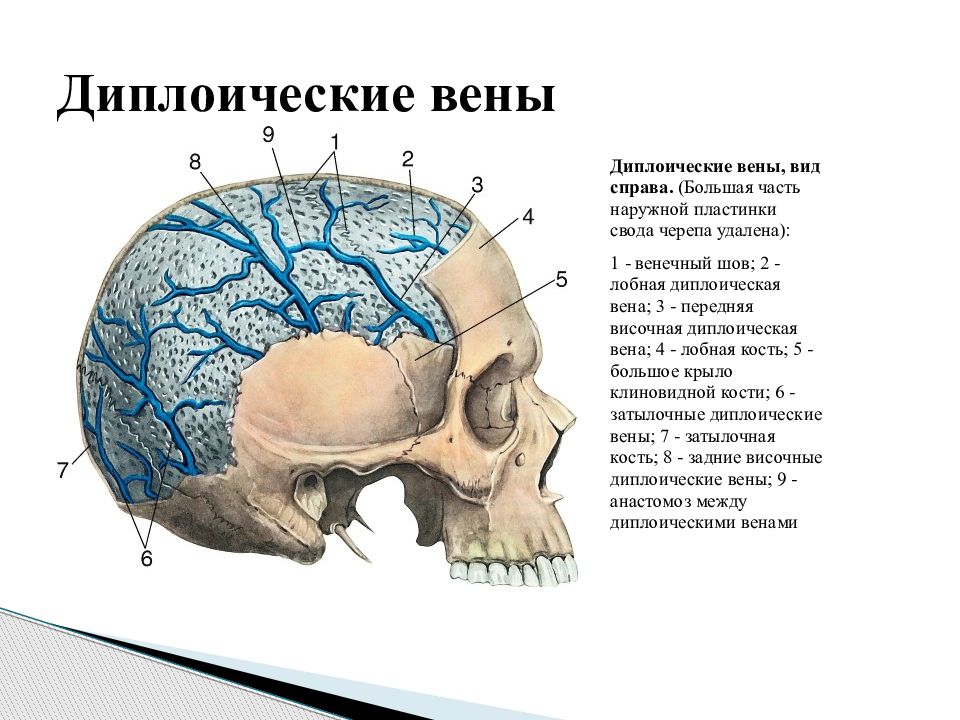

Анатомия детского черепа: Рентгеновские снимки и описание